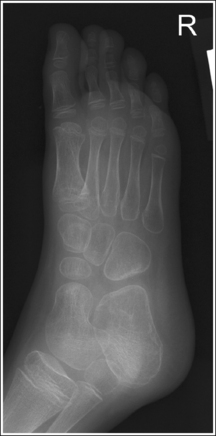

Foot: Anteroposterior Axial Projection (Dorsoplantar),

Foot: Anteroposterior Oblique Projection (Medial Rotation),

See Figure 6-12 and Box 6-5.

The foot demonstrates uniform density across the phalanges, metatarsals, and tarsals.

The foot demonstrates an AP projection. The joint space between the medial (first) and intermediate (second) cuneiforms is open, approximately 0.75 inch (2 cm) of the calcaneus is demonstrated without talar superimposition, and concavity on both sides of the first metatarsal midshaft is equal.

• An AP projection of the foot is obtained by flexing the supine patient's knee and placing the plantar foot surface against the IR (Figure 6-14). The lower leg, ankle, and foot should remain aligned, and equal pressure should be applied across the plantar surface.

The tarsometatarsal (TMT) and navicular-cuneiform joint spaces are open.

• The bones of the foot, with their ligamentous and muscular structures, are arranged in a longitudinal arch that is visible on the medial foot surface. This arch places the tarsometatarsal and navicular-cuneiform joint spaces at a set angle with the IR. To demonstrate these joints as open spaces, angle the central ray until it is aligned parallel with them. This is accomplished in most patients by using a 10- to 15-degree proximal (toward the calcaneus) angle or aligning the central ray perpendicularly with the dorsal surface. The exact degree of angulation needed depends on the height of the longitudinal arch. A 10-degree angle should be used when the patient's longitudinal arch is low, as shown in Figure 6-15. A 15-degree angle is needed in a patient with a high arch, as shown in Figure 6-16. Higher arched patients require a slightly higher angle. Omitting or employing an inaccurate central ray angulation results in obstructed TMT and navicular-cuneiform joint spaces (see Image 14).

The third metatarsal base is at the center of the exposure field. The proximal calcaneus, talar neck, tarsals, metatarsals, phalanges, and surrounding foot soft tissue are included within the collimated field.

• To place the third metatarsal base in the center of the image, center the central ray to the midline of the foot at a level 0.5 inch (1.25 cm) distal to the fifth metatarsal tuberosity. The fifth metatarsal tuberosity can be palpated along the lateral foot surface, approximately halfway between the ball of the foot and the calcaneus.